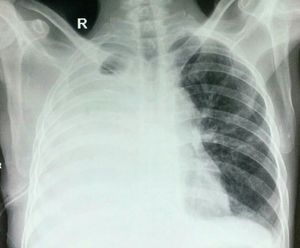

Pls interpret the chest x ray

Pneumothorax to left lung?

Massive pleural effusion?